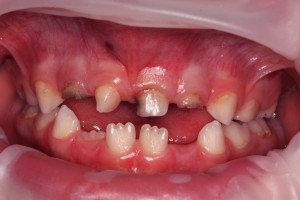

Chłopczyk w wieku 5,5 lat został skierowany przez ortodontę do placówki Stomatologia Bez Bólu z Jeleniej Góry w celu konsultacji i leczenia zaburzenia w okolicy zębów centralnych. Anomalia została wykryta na podstawie zdjęcia pantomograficznego, standardowo wykonywanego przed leczeniem ortodontycznym.

Po badaniu wewnątrzustnym stwierdzono uzębienie mieszane, adekwatne do wieku rozwojowego, bez czynnych ognisk próchnicowych. Zlecono badanie CBCT w celu dokładniejszej diagnostyki lokalizacji i liczebności przednich zębów w szczęce. W obrazie tomograficznym ukazał się od strony szczytu wyrostka, położony ząb nadliczbowy (mesiodens). Mezjodens w tym przypadku zajął miejsce stałego siekacza prawego, powodując jego dystorotacje. Usunięcia mezjodensa umożliwi wyrzniecie się zęba stałego we właściwej pozycji nie wykluczone jest wspomaganie ortodontyczne w celu ustanowieniu właściwej lokalizacji stałego zęba siecznego.

Plan leczenia zakładał usunięcie mesiodens’a z dojściem od strony szczytu wyrostka. W znieczuleniu nasiękowym CYTOKARTIN (1/3 ampułki) przeprowadzoną prostą ekstrakcję zębową zaopatrzono gąbką kolagenową.